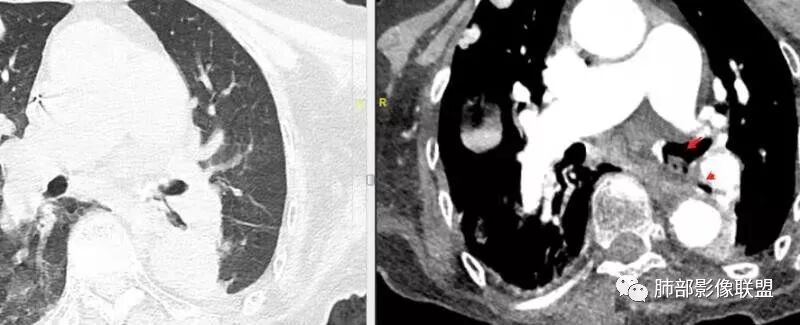

老年女性,间断咯血两年。影像:气管内带蒂结节,边缘光滑明显强化。左肺下叶背段支气管截断,远端不张。两肺散在大小不等结节及磨玻璃影,明显强化,磨玻璃影考虑合并出血可能。纵隔多发淋巴结肿大,两侧支气管受压。综合考虑:肺癌伴两肺转移。原发气管结节还是左肺下叶背段?腺样囊性癌?类癌?

老年女性,气管腔内占位,左肺下叶阻塞性炎症伴不张,腔外病灶大于腔内,左肺门血管包埋,外缘欠光滑,似有冰山征。纵隔淋巴结,双肺多发富血供团块样转移结节。

欣:

左肺下叶后基底段段气管变窄,远端可见片状影,有强化。这个地方不踏实,不排除占位性病变。双肺内多发界清结节,明显强化,富血供转移瘤?气管内结节,明显强化,边界清楚,和肺内多发结节一样明显强化,是不是要同源转移考虑?气管内转移瘤真没见过,还是考虑气管内占位?原发肿瘤在左肺下叶后基底段?还是其他部位?不好定。

左下叶考虑支气管腔内粘液栓堵塞所致